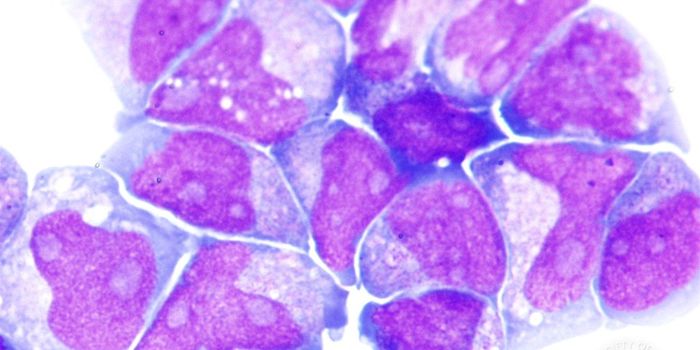

MAY 17, 2022CancerMuch has been written about scaling up cell culture for bioprocessing and other applications that require a very high de ...

OCT 31, 2019CancerIn a recent issue of Nature, the findings of one study made a particularly big splash: how and why cancer cells use ener ...

OCT 17, 2020Cell & Molecular BiologyScientists have found that our immune system has a surprising helper: droplets of fat that sit inside cells.

APR 29, 2016Cell & Molecular BiologyStarving immune cells of key nutrients thwarts their ability to launch an allergic response, according to new resea ...